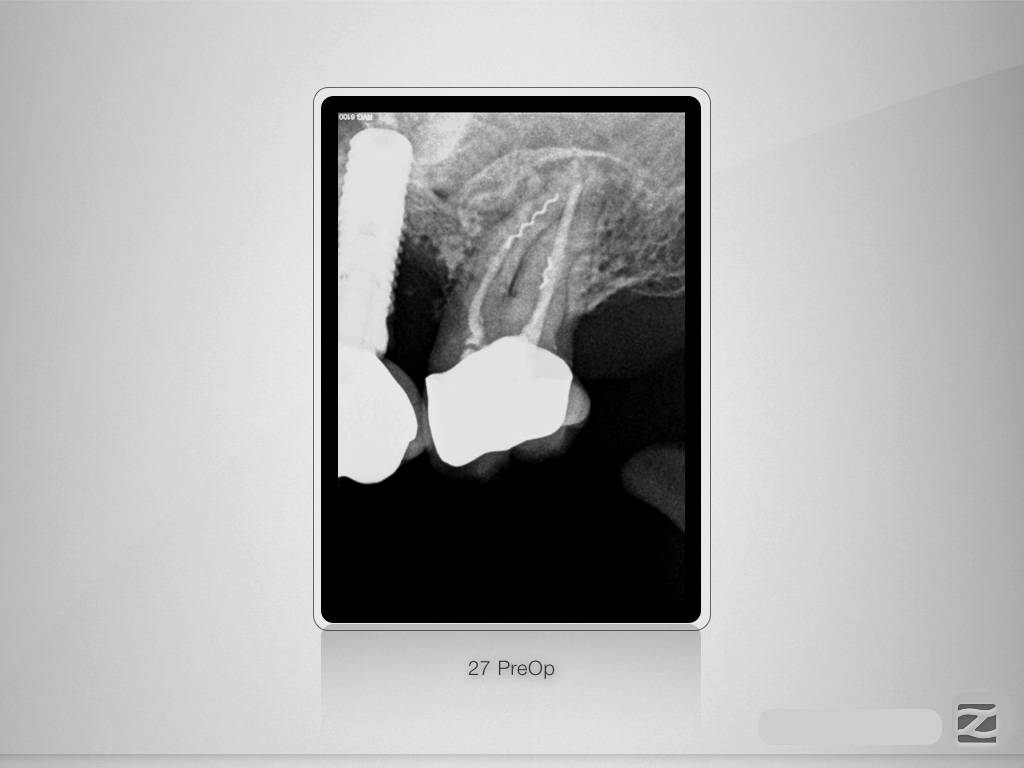

27E.001

„Navigierte“ Fragmententfernung